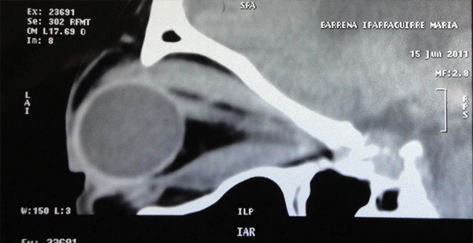

Resonancia magnética nuclear que muestra proptosis severa del globo ocular.